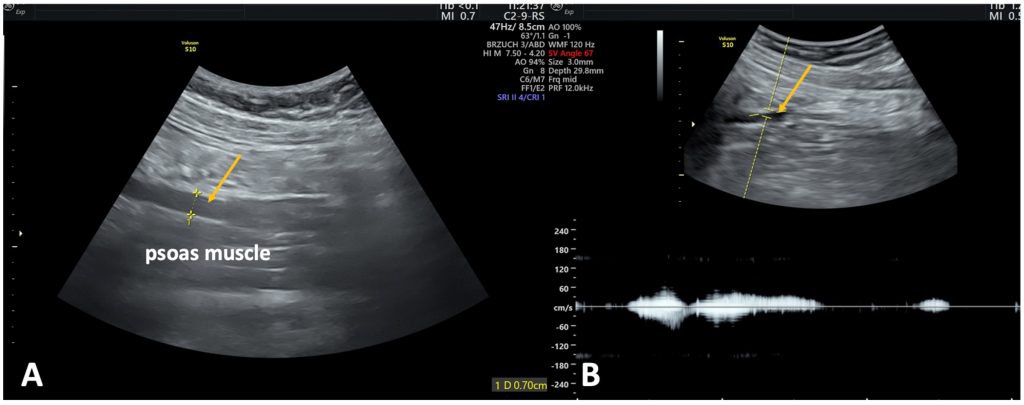

1.2. Паховая точка выхода является вторым по распространенности дренажным путем, встречающимся примерно у 20–35 % пациентов. Рефлюкс распространяется по венам круглой связки матки, которая проходит вдоль пахового канала. УЗИ должно включать осмотр пахового канала (области над паховой связкой и позади апоневротической части наружной косой мышцы живота). (рис.2)

Лечение варикозных вен тазового происхождения у пациенток

Рисунок 2. (A) Точка сброса выглядит как область с гипоэхогенной губчатой тканью. (B) При ЦДК визуализируется двунаправленный или турбулентный поток, характеризующийся чередованием цветовых сигналов. (С) При импульсно-волновой допплерографии можно наблюдать ретроградный компонент кровотока, сохраняющийся более 7 секунд.